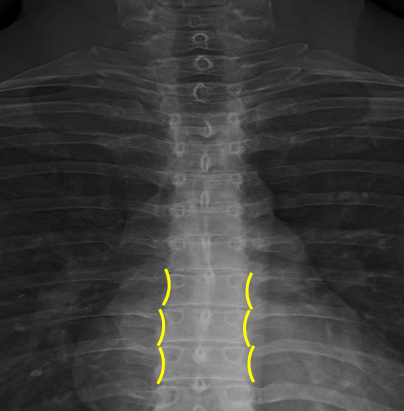

Femur heads

Superior iliac crests

Lateral iliac crests

Ischial tuberosities

Obturator foramen

S2 tubercle

Pubic symphysis

Sacral groove

Lateral aspect of sacrum

Medial aspect of ilium